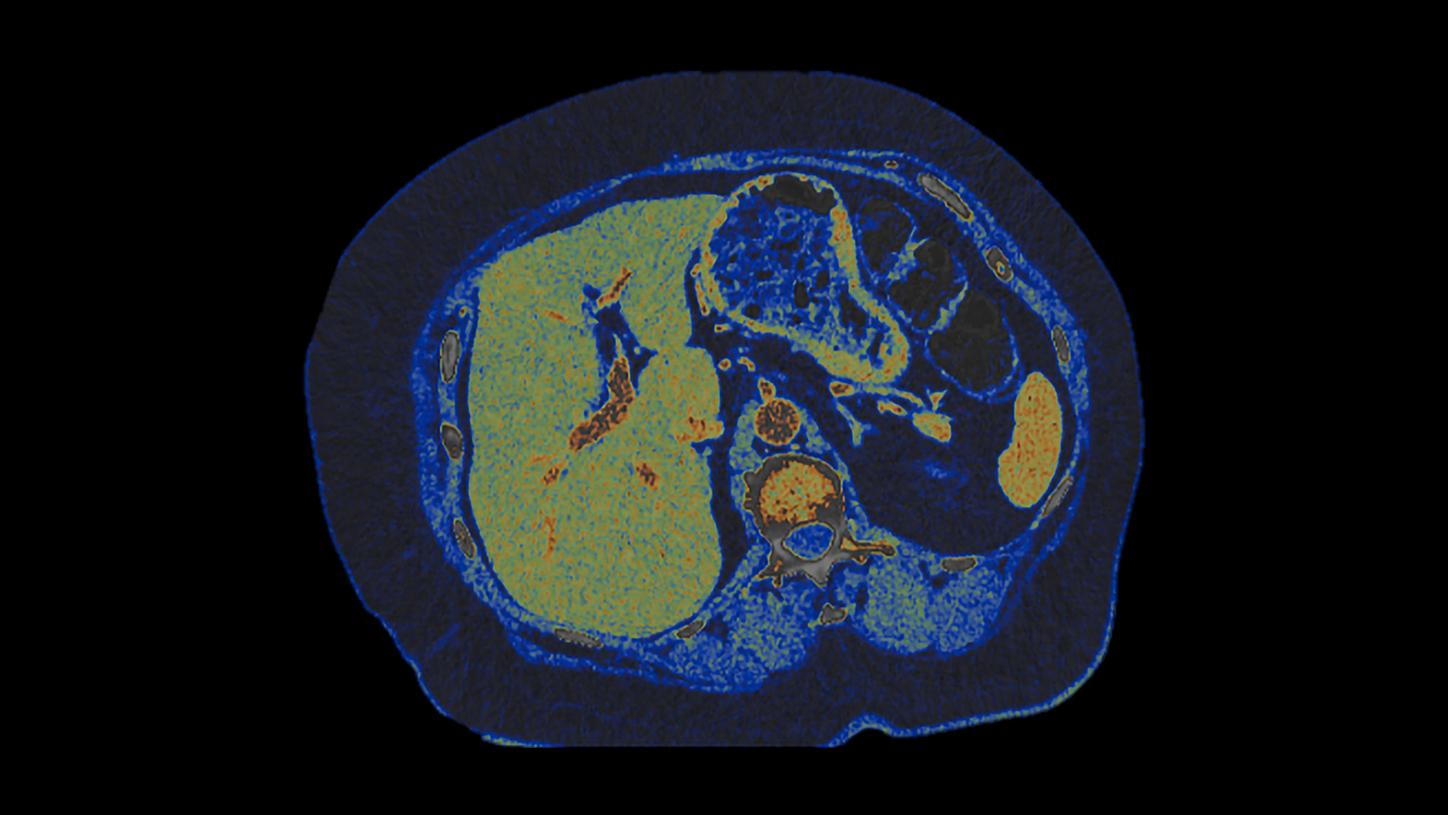

At the heart of NAEOTOM Alpha® is a radically new photon-counting detector. The QuantaMax detector directly converts X-rays into an electrical signal, which is then used to create an image. The energy of each X-ray is measured, so spectral information is available for every scan, and the images are contrast-rich with high spatial resolution at the same dose. Combining the high spatial resolution of the QuantaMax photon-counting detector with our Dual Source temporal resolution enables the visualization of fine details for increased diagnostic confidence.

QuantaMax, the first photon-counting detector, overcomes the limitations of conventional CT detectors by providing data at high spatial resolution, without electronic noise and with improved contrast-to-noise ratio.